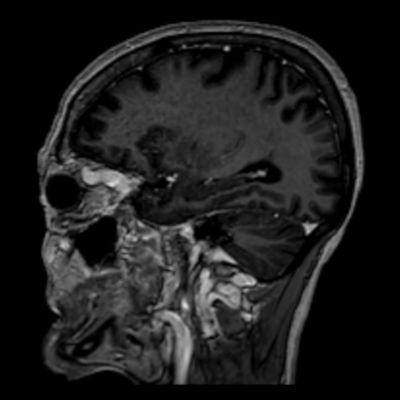

- A) Orbital MRG’de yağ baskılı T2A görüntülerde sol orbital globta ekzoftalmus (ok) izlenmiş olup retrobulbar yağlı dokuda kirlenmeler (ok) ve dilate superior oftalmik ven (ok) dikkati çekiyor. Beyin MRG’de kontrastlı T1A görüntüde sol kavernöz sinüste simetriğine oranla genişleme (ok) izleniyor.

- BT ve MRG: Propitozis, ekstraokuler kaslarda genişleme, superior oftalmik vende genişleme ve tortiyozite, ipsilateral kavernöz sinüste genişleme gösterilebilir. Serebral venöz konjesyonu olan ve intrakraniyal basınçları yükselen hastalarda serebral ödem, hemoraji, leptomeningeal ve kortikal venlerin dilastasyonunu görülebilir. Bunlara ek olarak travmaya sekonder olgularda BT ile eşlik eden fraktürler gösterilebilir.